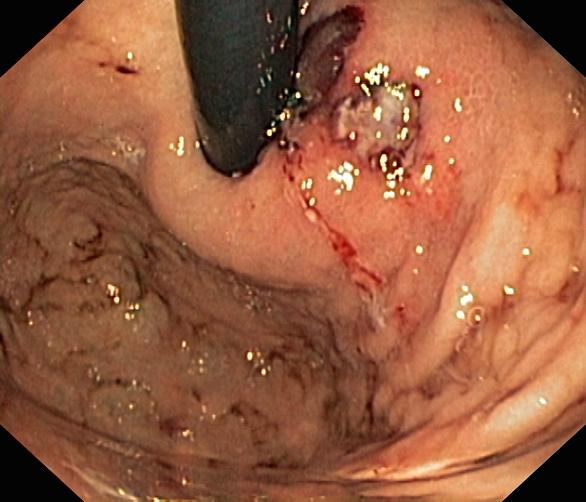

Krwawienie